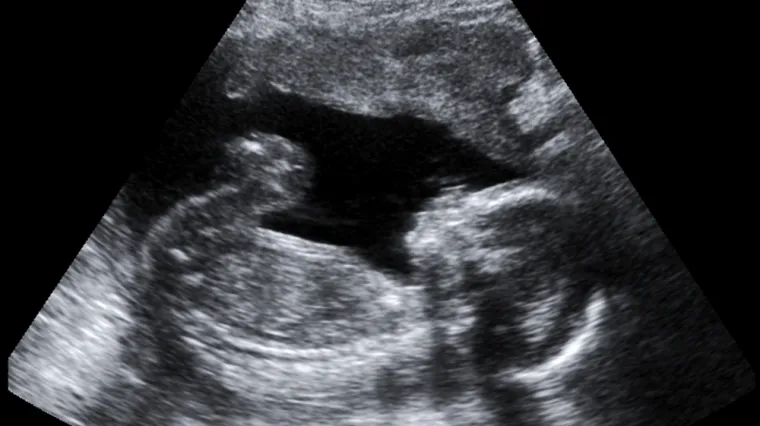

Tragičan slučaj u Portugalu. Roditelji malenog Rodriga nisu bili svjesni fizičkih abnormalnosti svog sinčića dok se nije rodio početkom ovog mjeseca. Rodrigo je rođen 7. listopada u bolnici u gradu Setubalu, oko 40 kilometara udaljenom od Lisabona. Njegova majka bila je na tri ultrazvuka tijekom tudnoće u privatnoj klinici, a ginekolog Artur Carvalho nikada nije rekao da nešto s njezinim djetetom nije u redu. Bila je i na četvrtom 5D ultrazvuku u drugoj klinici kada je bila trudna šest mjeseci kada joj je rečeno da bi dijete moglo imati određene abnormalnosti, međutim dr. Carvalho je odbacio njihovu zabrinutost.